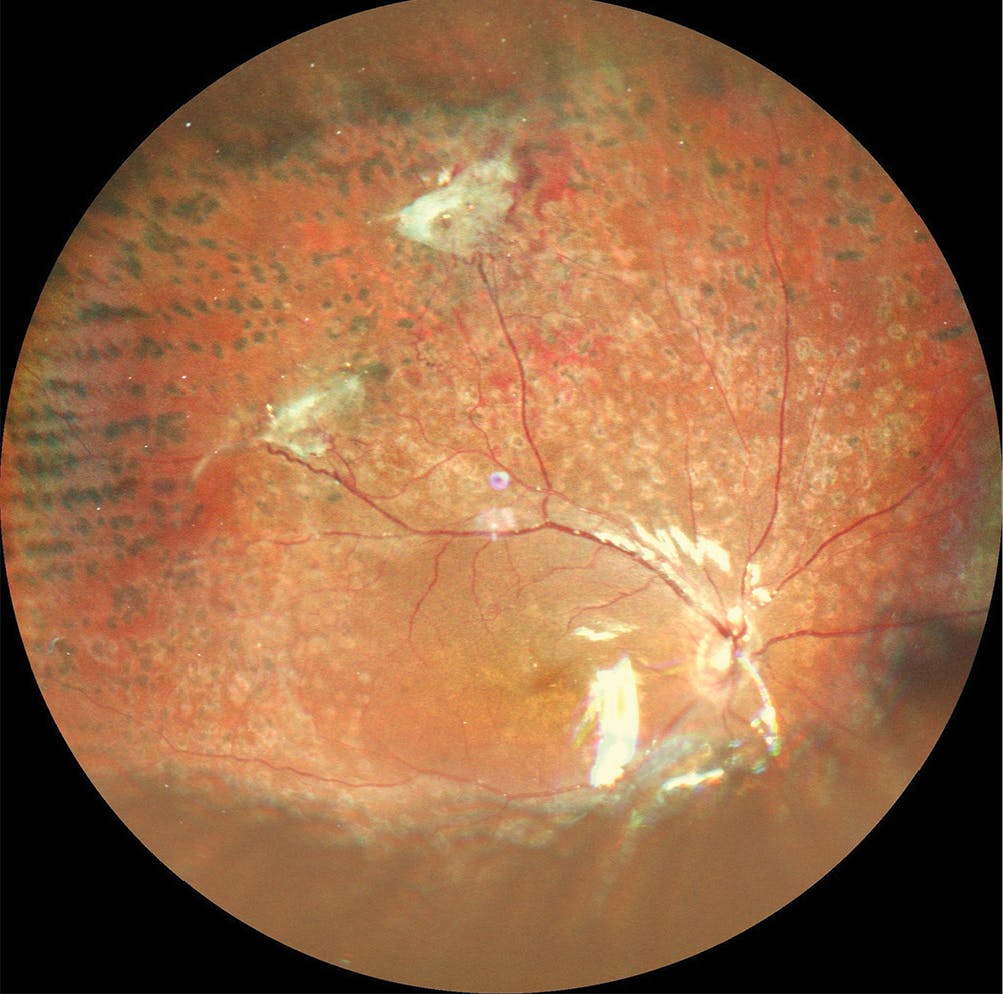

<p>Figure 1. A Mirante 163°* ultra-widefield color image of a right eye with diabetic retinopathy taken from the temporal position when the patient presented in early 2023. The image shows fibrovascular traction in the near periphery, temporally, and superiorly, and a subhyaloid hemorrhage. Laser scars are also visible for 360°.</p>

Figure 1. A Mirante 163°* ultra-widefield color image of a right eye with diabetic retinopathy taken from the temporal position when the patient presented in early 2023. The image shows fibrovascular traction in the near periphery, temporally, and superiorly, and a subhyaloid hemorrhage. Laser scars are also visible for 360°.

A 25-year-old female patient presented to our clinic at the Instituto Mexicano de Oftalmología I.A.P. (Santiago de Querétero, Mexico) in early 2023 with diabetic retinopathy in the right eye (Figure 1) and macular atrophy in the left eye (Figure 2). She had undergone surgery 1 year prior for tractional retinal detachment in the left eye, after which the vision was counting fingers at 30 cm.

My team and I used the Mirante to capture multimodal imaging of the right eye, including ultra-widefield color images and green fundus autofluorescence (FAF). These showed fibrovascular proliferation in the temporal periphery. Also present was a subhyaloid hemorrhage in the posterior pole (Figure 1), and because this configuration increases the risk of acute contraction (the so-called “crunch”) after anti-VEGF injections or laser treatment, these interventions must be used cautiously. Her vision was 20/25 BCVA in the right eye. We decided to treat this eye with vitrectomy with silicone oil, after which her vision stabilized at 20/60 UCVA for 2 to 3 months.